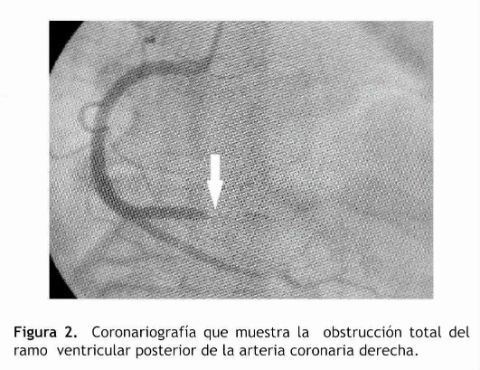

Se administra tratamiento con aspirina, clopidogrel, enoxaparina, propranolol y nitroglicerina. La paciente continúa dolor precordial, realizándose una angiografía hallándose: Coronaria derecha dominante.

Oclusión total aguda de ramo ventricular posterior en tercio proximal (Figura 2). Se realiza angioplastia con balón y aspiración de trombo recuperándose flujo TIMI 3 Figura 3

Los hallazgos muestran la presencia de coágulo obstructivo total de la arteria coronaria derecha (CD) en su ramo ventricular posterior, de allí la presencia del segmento ST deprimido como espejo de la elevación ST en la cara posterior del ventrículo izquierdo.

Se realizó una trombo aspiración durante el procedimiento con la restauración del flujo coronario TIMI 3 sin presencia de lesiones ateromatosas significativas. Los constituyentes principales del trombo que se producen en las venas y las cámaras cardiacas son los glóbulos rojos y fibrina, por lo tanto su apariencia macroscópica es roja.